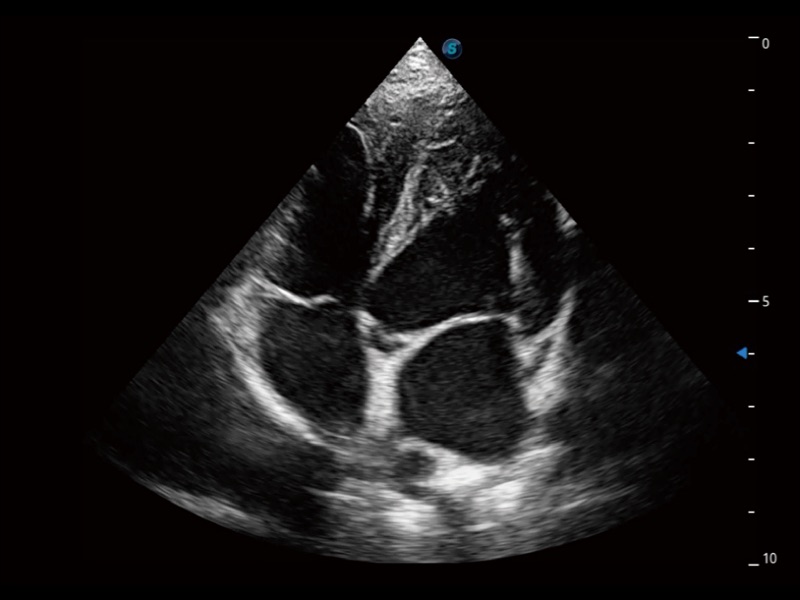

能够基于左心室壁追踪和辛普森法,自动计算射血分数,支持多个可移动点描迹,与手动测量相比,极大节省了动物医生的时间和精力。

具备多种协议可选,同时支持17阶段划分法和专业的SE报告。

通过360度任意调节3条M型取样线,在同一心动周期上观察心脏不同位置的运动曲线,得到准确的心功能测量数据,有效评估心肌运动及左心室功能。

实时用颜色表示心肌组织运动,观察和定量组织的运动情况,对快速检测与评估心肌的灌注和活性、电传导及心肌收缩和舒张功能等均能提供重要的诊断信息。

当心脏测量结果超出正常范围时,可实时预警提示动物医生,减少疾病漏诊概率。